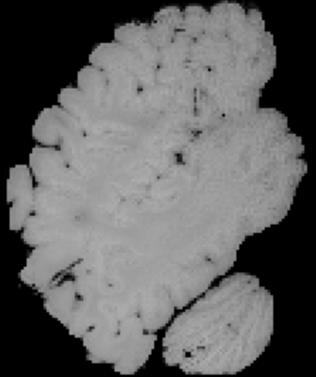

In neuroimaging, MRI tissue properties characterize underlying neurobiology, provide quantitative biomarkers for neurological disease detection and analysis, and can be used to synthesize arbitrary MRI contrasts. Estimating tissue properties from a single scan session using a protocol available on all clinical scanners promises to reduce scan time and cost, enable quantitative analysis in routine clinical scans and provide scan-independent biomarkers of disease. However, existing tissue properties estimation methods - most often $\mathbf{T_1}$ relaxation, $\mathbf{T_2^*}$ relaxation, and proton density ($\mathbf{PD}$) - require data from multiple scan sessions and cannot estimate all properties from a single clinically available MRI protocol such as the multiecho MRI scan. In addition, the widespread use of non-standard acquisition parameters across clinical imaging sites require estimation methods that can generalize across varying scanner parameters. However, existing learning methods are acquisition protocol specific and cannot estimate from heterogenous clinical data from different imaging sites. In this work we propose an unsupervised deep-learning strategy that employs MRI physics to estimate all three tissue properties from a single multiecho MRI scan session, and generalizes across varying acquisition parameters. The proposed strategy optimizes accurate synthesis of new MRI contrasts from estimated latent tissue properties, enabling unsupervised training, we also employ random acquisition parameters during training to achieve acquisition generalization. We provide the first demonstration of estimating all tissue properties from a single multiecho scan session. We demonstrate improved accuracy and generalizability for tissue property estimation and MRI synthesis.